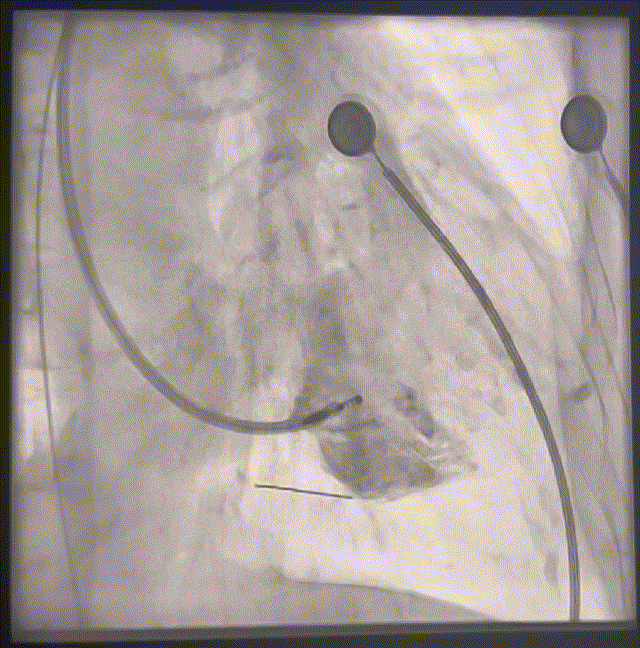

术中影像下最后确认植入位点

图5

术后即刻参数QRS:99ms,达峰时间:74ms,SV:21ms。